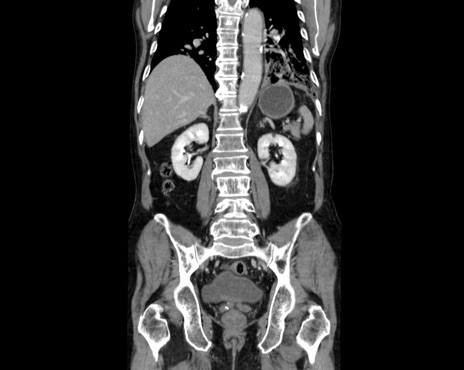

症例26(冠状断像)

【症例】80歳代男性

【主訴】嘔吐

【現病歴】昨晩2回嘔吐あり、今朝になっても嘔吐あり。来院。

【既往歴】胃潰瘍

【身体所見】意識清明、BT 37.6℃、BP 166/95mmHg、HR 100bpm、SpO2 97%、腹部:平坦・軟、腸蠕動音聴取良好、圧痛なし。

【データ】WBC 21900、CRP 1.4